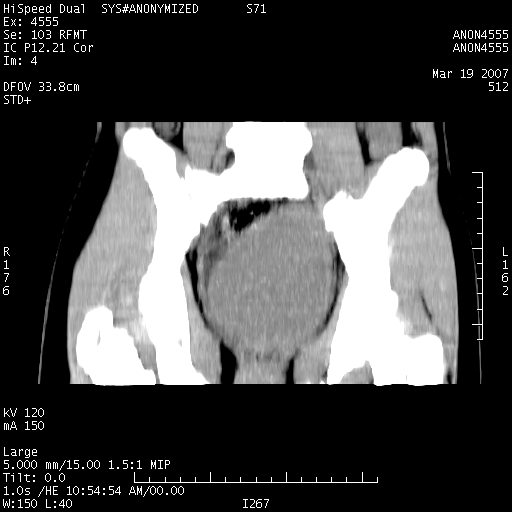

女,14岁,腹痛腹胀月余,患者发育正常,无月经史,检查发现下腹部肿块。患者碘过敏试验阳性。

子宫处见大的软组织肿块,考虑患者女性、14岁无月经,怀疑子宫发育异常

处女膜闭锁,阴道积血。

从矢状位上可见阴道部位明显增粗,内容密度较低,结合患者年龄和临床表现,首先考虑为先天性处女膜闭锁。

处女膜闭锁,阴道、子宫积血。

结合病史考虑处女膜闭锁致阴道、子宫积血。

处女膜闭锁致阴道、子宫积血。

考虑为先天性处女膜闭锁所致的阴道及子宫积血